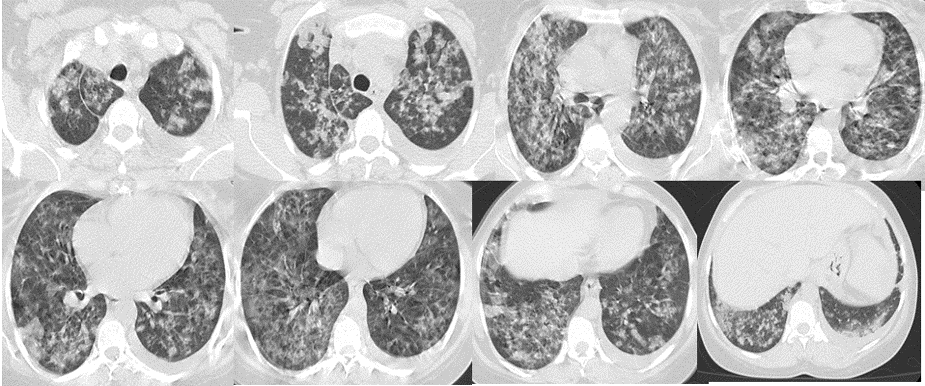

Femme, 45 ans, Suivie pour LAM depuis un mois

Hospitalisée depuis une semaine pour une chimiothérapie d’induction (Aracytine + anthracycline)

Bilan à l’admission

GB: 173 190/ul, Hb: 6g/dl, Pq: 30 000/ul, CRP: 202mg/L, TP: 57%

Apres 5 jours:

Dyspnée stade IV sans douleurs thoraciques, Hémoptysie de grande abondance

Apyrétique, SaO2: 84% , TA: 12/8, FC: 120 bpm, FR: 30

QUEL EST VOTRE DIAGNOSTIC ?